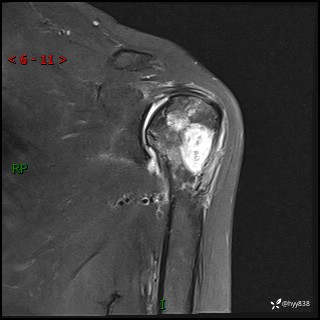

肱骨MRI平扫(axi T1WI+cor T2WI-fs)+CE-fs(COR+SAG)